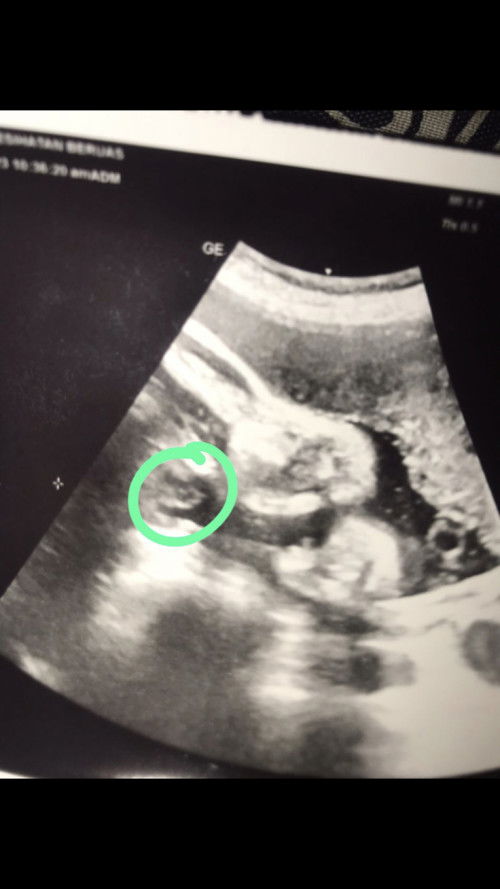

Hi. Saya nak mintak pendapat semua. Saya EDD 30/11 ni. tapi mak mertua ajak ke Langkawi naik boat 11 dan 12/11 which is 2 week before due date la kan. Patut ke saya pergi? Ada risiko tak naik boat 2week before due?? 😅 Saya dari kedah je, pergi langkawi pn sbb ada kenduri sedara. Kalau ikutkan mmg tak larat la nak pergi, takut pulak terberanak dkt sana #pleasehelp